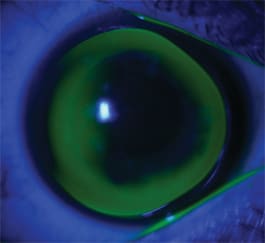

Patient #2 is a 30-year-old office clerk. Six years ago he underwent a corneal transplantation procedure in his right eye due to severe keratoconus. Due to cataract, he also had a monofocal IOL implanted in the same eye. Figure 5 shows the graft from his right eye, and Figure 6 shows the corneal topography in which the tilt of the graft is evident. He already wore GP lenses, but because of the monofocal intraocular lens and the lack of accommodation, his near vision was far from satisfactory.

Figure 5. Graft in right eye of Patient #2.

The optical zone of this lens was multifocal, with a central zone of 5.50mm with –1.50D power for distance vision and an aspheric transition up to 8.50mm, which provided an add of +2.00D. We selected the power of the add and the width of the progressive zone by measuring the photopic and scotopic pupil and observing the upward movement of the contact lens at downward gaze when the patient was reading. This lens provided 20/25 distance vision and, more importantly, J2 at near. Figure 7 shows the fitting relationship. The lens edge touches the cornea nasally, in areas which correlate with the tilt seen on the topography. Although vision is more than satisfactory, we need to closely monitor this patient to avoid complications. CLS

Figure 7. Fitting relationship OD for Patient #2.